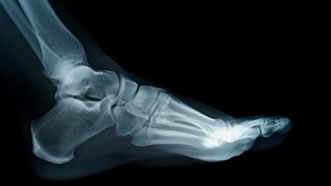

Highly active people (athletes in particular), or those with a very sedentary lifestyle, are very prone to stress fractures. When muscles weaken—either from too much or too little use—the muscles cease providing cushion for the foot and as they impact the ground. As there is very little to protect the bones in your feet, each step you take causes the bones to absorb the full impact, and this causes cracks to form, or stress fractures, to form in the pressurized bones.

At the localized site of the fracture (typically where the symptoms originate) the pain can be immense. Sharp or dull pain is paired with swelling and possibly tenderness—engaging in any kind of further activity, especially high-impact, is highly discouraged. Though stress fractures heal in time, they are not as serious as say, when you receive one and continue engaging in high-impact activity; the condition may turn into a full fracture. A full fracture is very serious and may prevent usage of the foot wholesale.

From this point, treatment can vary patient to patient with the severity of the fracture. Rest is absolutely required for the foot. Fractures vary in healing time, some can be healed with short bursts of rest, and others require prolonged periods of resting paired with crutches. In cases in which the fracture is very serious, surgery may be authorized to install pins supporting the fracture and aiding in healing.